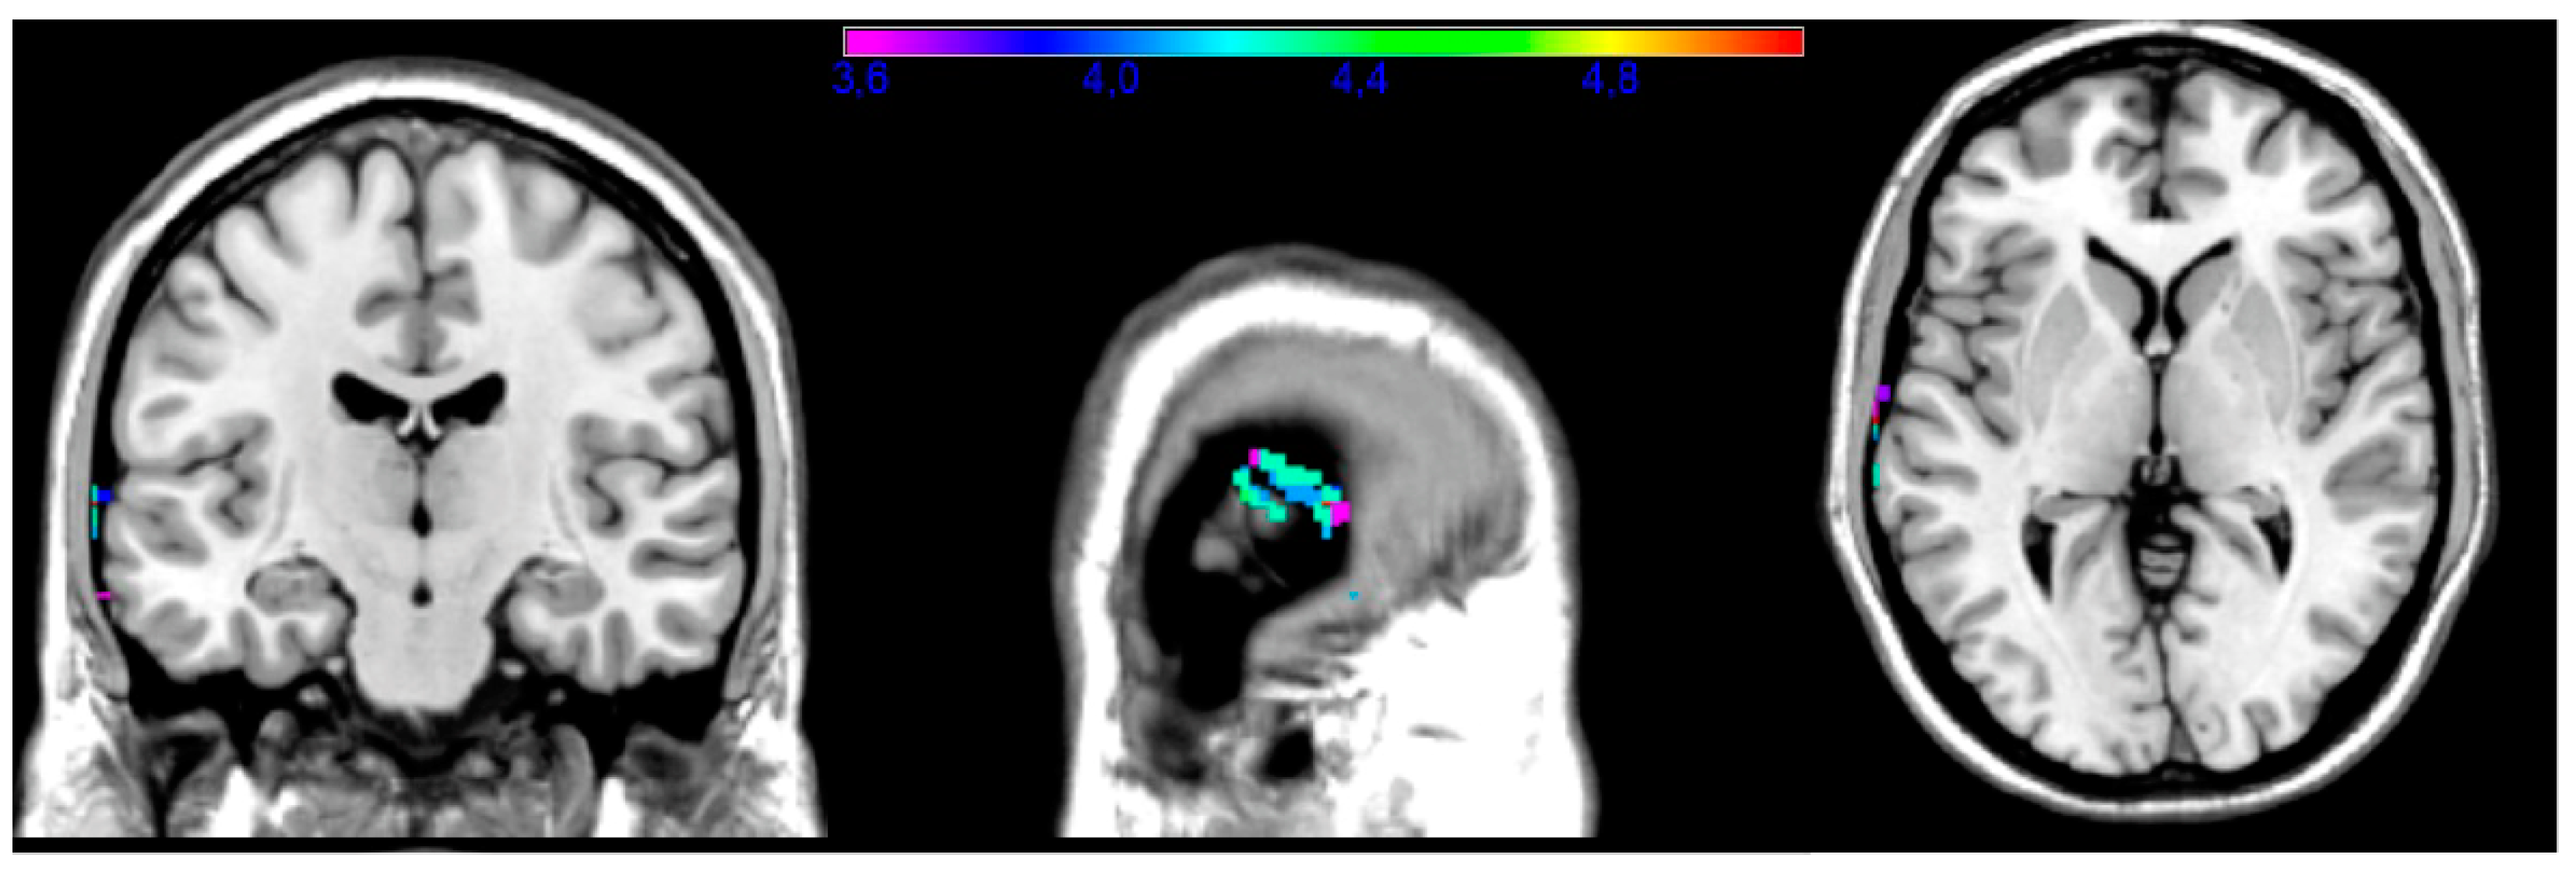

| Subtest | Volume | Px | Py | Pz | Min T | Max T |

|---|---|---|---|---|---|---|

| Facial | 88 | −50 | −34 | −20 | 3.67 | 5.58 |

| Upper limb | 68 | −72 | −16 | 2 | 3.57 | 5.1 |